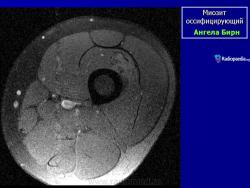

Рентгенологические признаки однотипны для всех форм оссифицирующего миозита; плотный рисунок периферической и менее плотный центральной части повреждения.

При компьютерной томографии визуализируется кальцификация гетеротопической кости, которая продвигается от наружного края образующегося узла в центр.

Рентгенологические признаки однотипны для всех форм оссифицирующего миозита; плотный рисунок периферической и менее плотный центральной части повреждения.